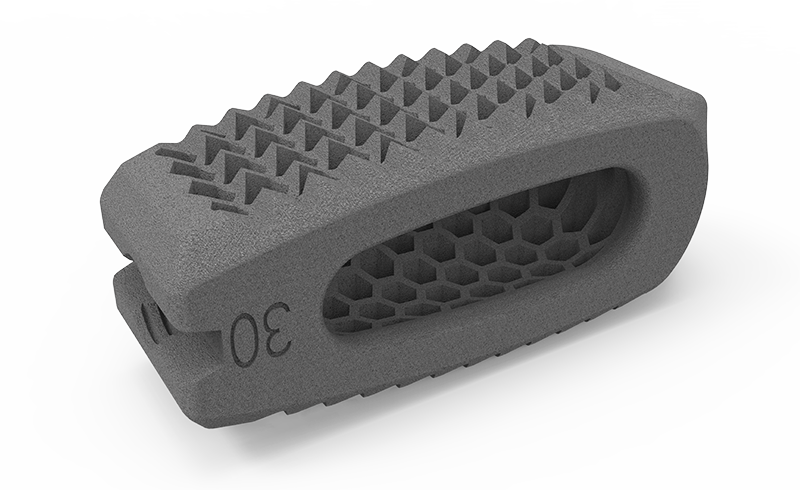

zurückDeltacorCages

Cages

Alle Modelle nun mit der patentierten hygroskopischen Struktur. Diese Kapillarwirkung beeinflusst das Einwachsverhalten positiv ohne Verwendung von autologem Knochen.